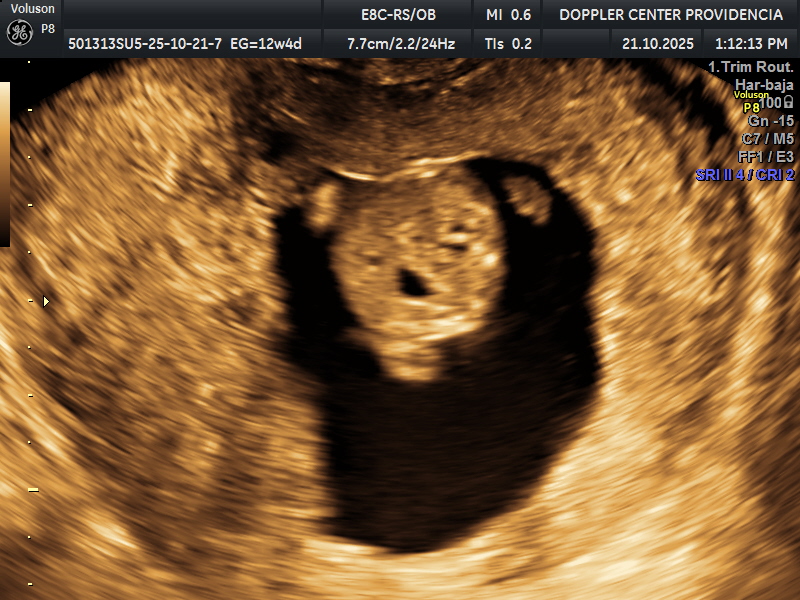

• Eco Doppler 11-14 semanas